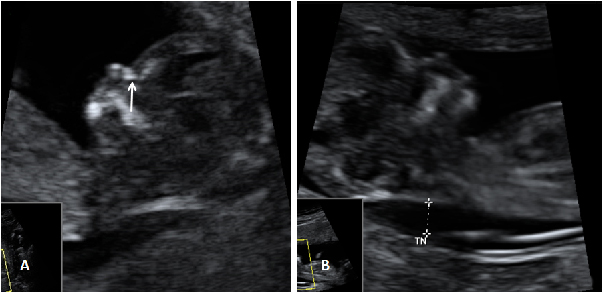

La ecografía Doppler permite comprobar el flujo sanguíneo en el feto y en el cordón umbilical, y así diagnosticar algunas enfermedades o malformaciones cardiacas, entre otras cosas.